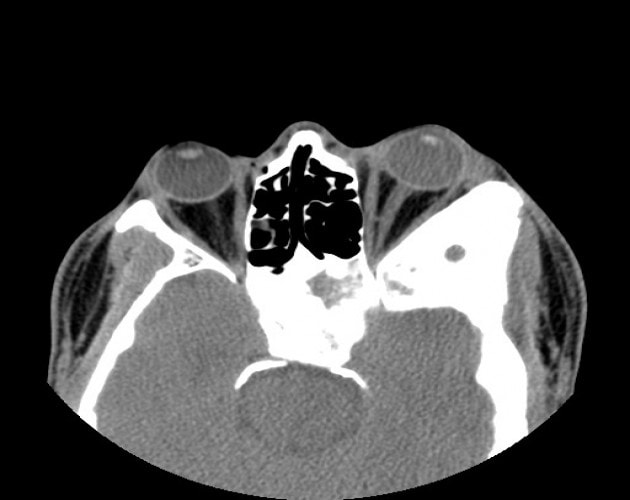

- CT scan detects an oval or round, homogenous mass with sharp margins, but falls short of a definitive diagnosis.

Imaging of Cavernous Hemangioma

- CT: smooth discrete lesion, fills with dye after 20 min; coronal cuts important to know tumor position relative to optic nerve. for sugical plan

- MRI: hypointense to fat on T1, hyperintense to fat on T2

- U/S: high reflectivity (A-scan high amplitude internal echoes)